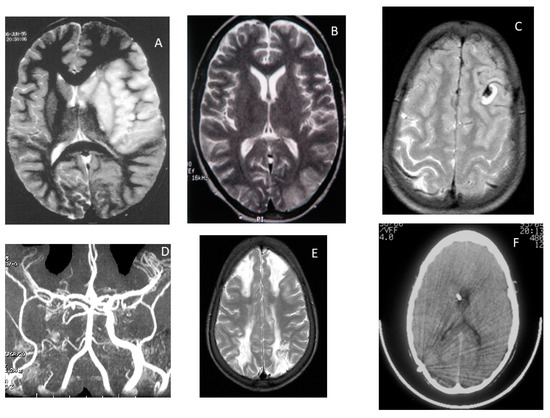

9.2. Cerebrovascular Disease on Magnetic Resonance Angiography